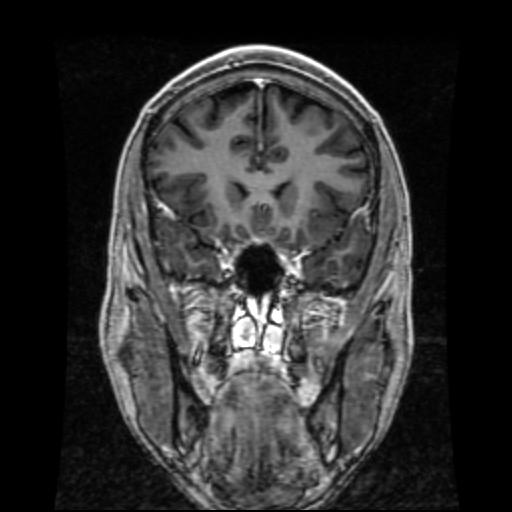

MRI Brain - Coronal

Cerebral Coronal Axis

Brain with Vertical Side to Side Cuts

T1-Weighting

This type of magnetic resonance imaging (MRI) study looks at the brain with 28 coronal (vertical - side to side) cuts that begin at the back of the brain and work forward.

T1-weighting causes the nerve connections of white matter to appear white, and the congregations of neurons of gray matter to appear gray, while cerebrospinal fluid (CSF) appears dark.